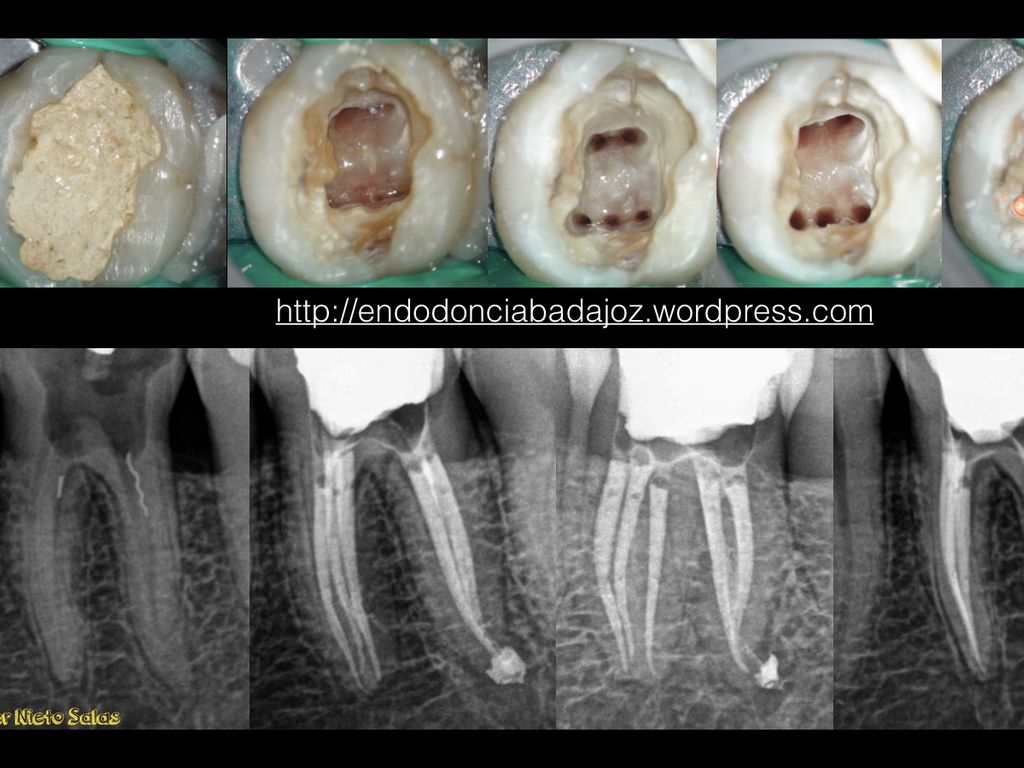

LIMPIEZA Y CONFORMACIÓN

Análisis Pre-Acceso

Remoción del techo de cámara pulpar

Identificación del piso pulpar y entrada de conductos

Instrumentación de los conductos

LEYES DE ACCESO

Ley de la centralidad

Ley de la concentricidad

Ley de Cambio de color

LOCALIZACIÓN DE CONDUCTOS

La entrada de los conductos radiculares SIEMPRE están localizados en la unión de las paredes y el piso

Una vez localizada la unión piso-pared de la cámara pulpar y se haya generado una forma, entonces la entrada de los conductos siempre estará en los vértices de esa forma.